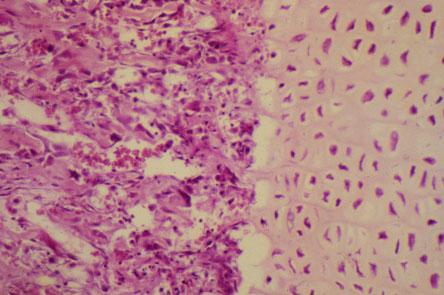

IV-41 (5) Slide 12, Endochondral Ossification (H&E). (continuation: R-L) Zone of hypertrophy, zone of calcification, metaphysis with zone of ossification and primitive bone marrow with bony spicules.